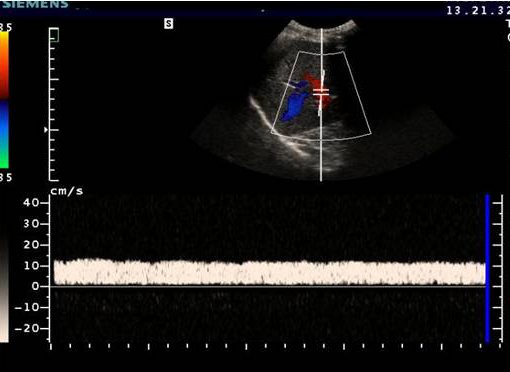

Asociado a esta masa, descendiendo por el canal inguinal, en la búsqueda del teste, encontramos un área donde unas estructuras tubulares y tortuosas de aspecto anecoico y móvil muy compatibles con varicocele, que ya hemos estudiado en el blog con anterioridad y compatibles con venas varicosas…

…con la aplicación del doppler color y la maniobra de valsalva confirmamos dicha sospecha para que el radiólogo tenga constancia del hallazgo. Marcamos siempre la maniobra, y colocamos siempre correctamente el pictograma como indica la flecha amarilla, recuerda que no solo la calidad de imagen debe ser el objetivo. El TSID trabaja para un radiólogo que revisará la imagen eco-anatómica y toda la información que nosotros podamos ofrecerle al margen usando textos y/o pictogramas en el contexto siempre de un protocolo como el que estoy contándote hoy.